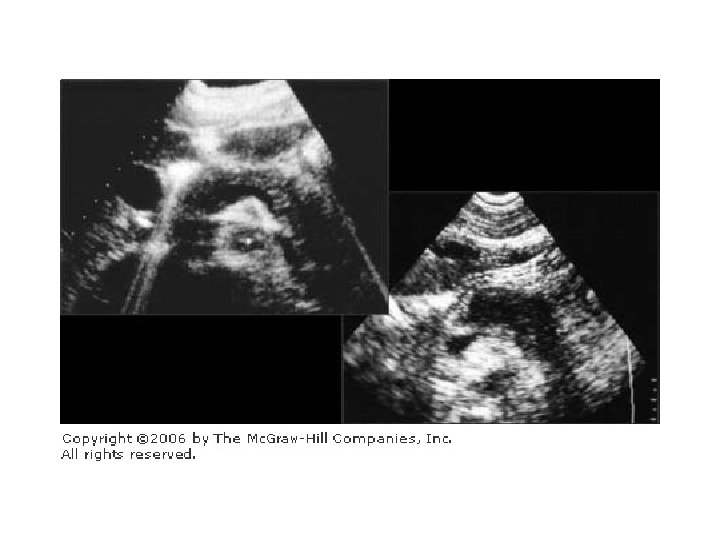

Karın USG • Safra kesesinde taş • Koledokolitiazis • Koledok genişlemesi

Psödokist • Fibröz duvarlı peripankreatik sıvı kolleksiyonudur. • 1 aydan daha uzun sürmesi • Kisti döşeyen epitel yoktur, kist içeriğinde yüksek amilaz düzeyi saptanır. • Akut sıvı kolleksiyonları psödokist değildir. • Akut pankreatitli hastaların %35 inde peripankreatik sıvı kolleksiyonu gelişir. • 50% den fazlası 3 ay içinde spontan olarak düzelir 6 haftadan sonra komplikasyon oranı artar. • Serum amilaz düzeyindeki yüksekliğin devam etmesi psödokisti düşündürmelidir. • Girişimler 6. haftadan itibaren yapılır

Psödokist sınıflaması • Tip 1 - normal duktal anatomi. Pankreatik duktus ile kist arasında fistül yoktur. • Tip 2 - Anormal duktal anatomi. Pankreatik duktus ile kist arasında fistül yoktur • Tip 3 - Anormal duktal anatomi. Pankreatik duktus ile kist arasında fistül vardır.

• Perkütan Drenaj: • Ultrasound ya da BT eşliğinde • Tip 1 kistlerde %80 başarılıdır. • Fistül varsa başarı daha azdır. • Nadiren pankreatik abse veya fistül gelişebilir. • Endoskopik drenaj+ Pigtail kateter yerleştirilmesi • Cerrahi drenaj • Kistogastrostomi • Roux Loop Kistojejunostomi • Kist duvarından biopsi, adenoca riski için.